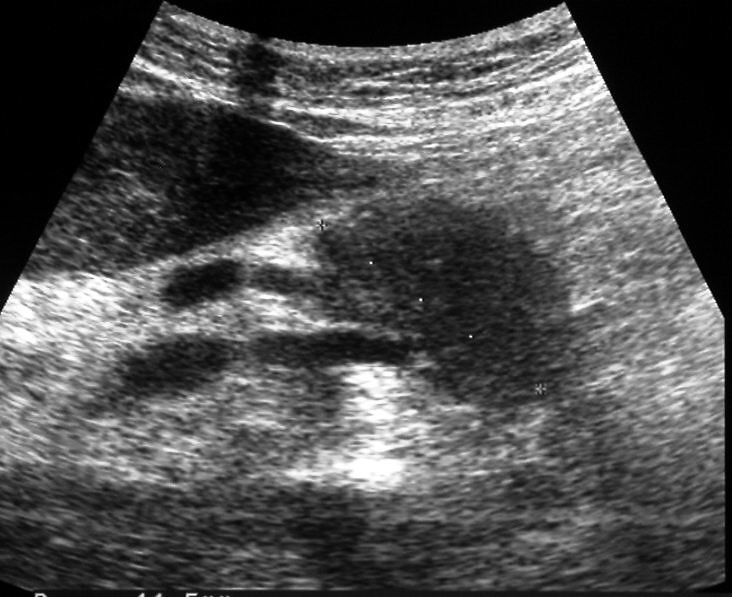

이 중 1가지 이상에 해당한다면 췌장암을 의심하고, 복부초음파, 복부CT, MRI, 내시경초음파 등 정밀검사를 받아보는 것이 좋습니다.